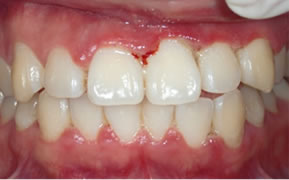

症例4

治療の特徴(患者I様)

初診時においては物を咬むと違和感が強く歯周外科処置を行いました。

骨のラインが部分的に増え、平坦にきれいに治っています。

2019年5月20日現在

歯周ポケット内をCPWで洗浄した時の変化

CPWによるイリゲーション前の状態

CPWによるイリゲーション後の状態

左の画像は、歯肉からの出血がある患者のものです。

歯周ポケット内をCPWを用いて治療しました。

右の画像は、治療後2週間後の口腔内の状態です。

(人によって個人差があります。あくまで一例です。)